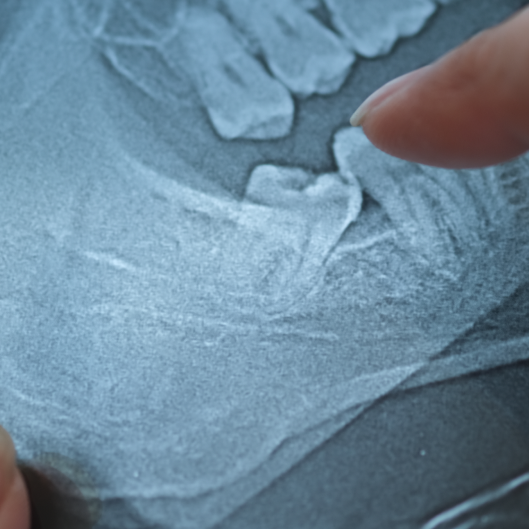

Why Remove Wisdom Teeth?

Wisdom teeth are the last set of molars to develop, typically appearing between ages 17 and 25. Without enough space to properly emerge, these teeth can cause crowding, decay, infections, and serious oral health complications. Proactive removal protects your smile and prevents future problems.

Wisdom Teeth Removal